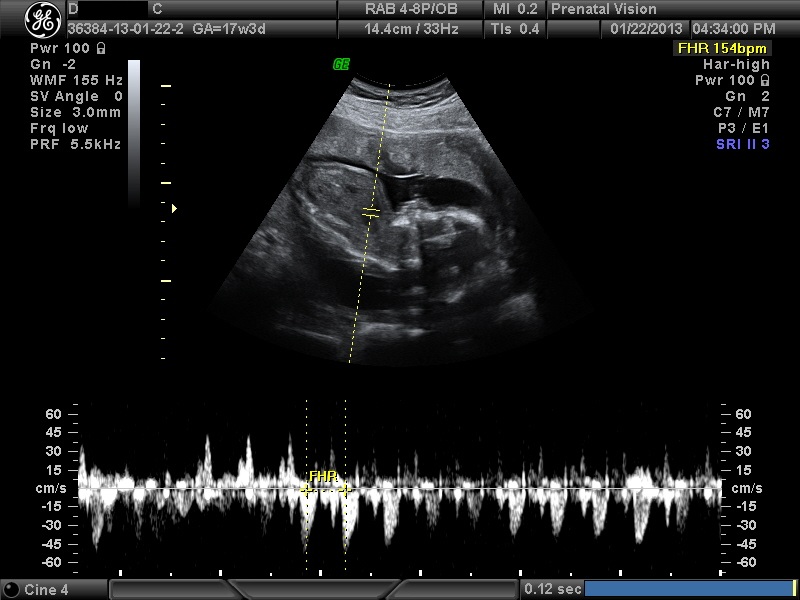

IMAGES_3 January 22, 2013 by Courtney Leave a comment ← Previous Image Next Image → 17w3d – Heartbeat of 154/155 bpm Like Loading...